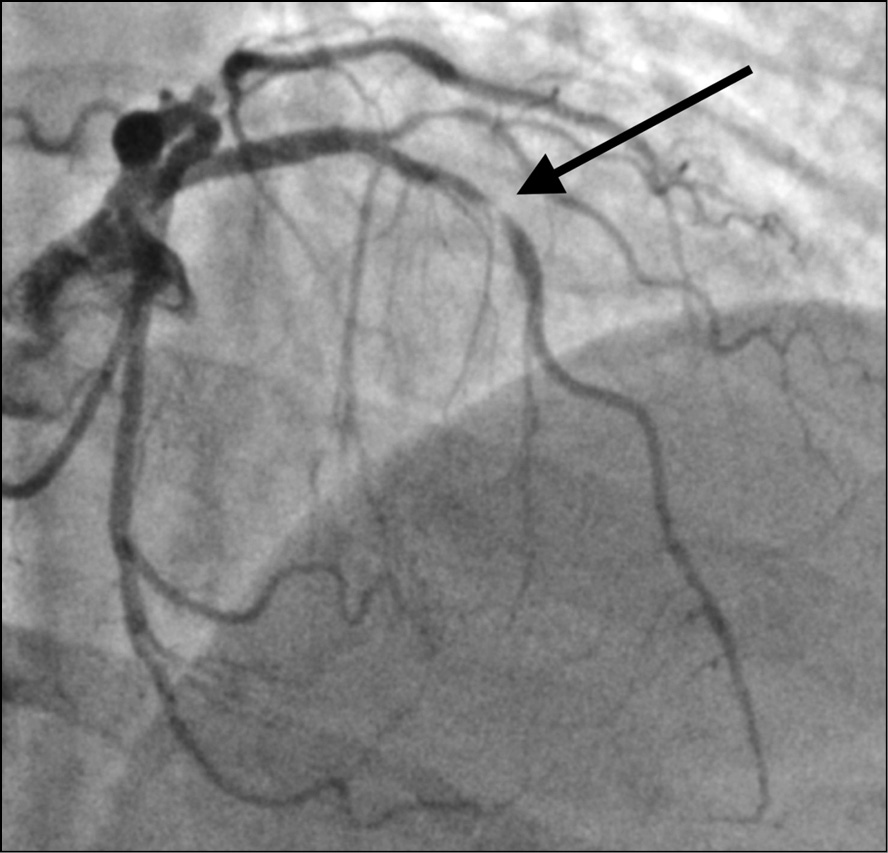

Выполнена коронарография трансрадиальным доступом, на которой выявлено многососудистое поражение коронарного русла: субокклюзия средней трети передней нисходящей артерии (рис. 2), субокклюзия устья первой ветви тупого края (рис. 3), субокклюзия проксимальной части правой коронарной артерии (рис. 4). Диаметр правой коронарной артерии менее 2 мм. Левый тип кровоснабжения миокарда. Тяжесть поражения коронарного русла по шкале Syntax 1 [3] составила 13 баллов (легкая). Рекомендованный метод реваскуляризации миокарда по шкале Syntax 2 [4] — аортокоронарное шунтирование (53,6 балла для чрескожного коронарного вмешательства и 28,6 баллов для аортокоронарного шунтирования).

Рис. 3. Пациентка Б., 64 года, с острым коронарным синдромом, находящаяся на программном гемодиализе: при коронарографии трансрадиальным доступом выявлена субокклюзия устья первой ветви тупого края (указана стрелкой)